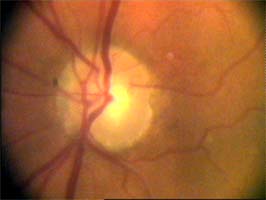

pacientka 1998

(tenze 40-50 torr) Na obrázcích vidíme terče levého oka pacientky, u které se ani opakovanými operacemi nepodařilo snížit nitrooční tlak.

pacientka 2001

Kromě zvětšení a vertikálního protažení exkavace je zřetelné zúžení arterií, zatímco vény jsou zúženy jen méně zřetelně.